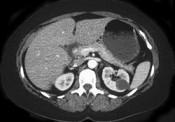

问题 女性,最近感腰部胀痛,体检发现B超右肾正常,左肾有一囊肿,双肾体积不增大,尿常规、肾功能正常,无家族病史,CT表现入图所示,最可能考虑为 ( )

选项 A.肾积水 B.多囊肾 C.多发性肾囊肿 D.肾肿瘤 E.肾结核

答案 C